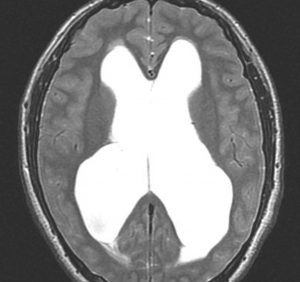

15歳時に水頭症で発症して増大しなかった例

この例が画像としては典型的な中脳視蓋グリオーマと言えます。手術摘出できないタイプです。

15歳の時に頭痛と嘔吐,視力と視野障害がでました。閉塞性水頭症だったので第3脳室開窓術を受けました。この時の診断は松果体腫瘍でした。でも翌年,開窓部が詰まってしまって,V-Pシャント(脳室腹腔短絡術)を受けました。でもシャントが詰まってしまって,頭痛と嘔吐と意識障害(昏睡、除脳硬直)を生じる急性シャント不全になり,シャント手術のやり直しをしました。21歳の時にもシャント不全で意識障害になり,シャント手術のやり直しをしました。その3ヶ月後にもまたシャント不全でシャント再建術を受けて,それから私の外来に来ました。

左はT1強調画像,右はFLAIR画像です。中脳視蓋が腫れて腫瘍がにじむように広がっているのがわかります。この腫瘍本体は15歳の時から21歳の時まで大きくなっていないので,中脳視蓋グリオーマ tectal gliomaの診断です。